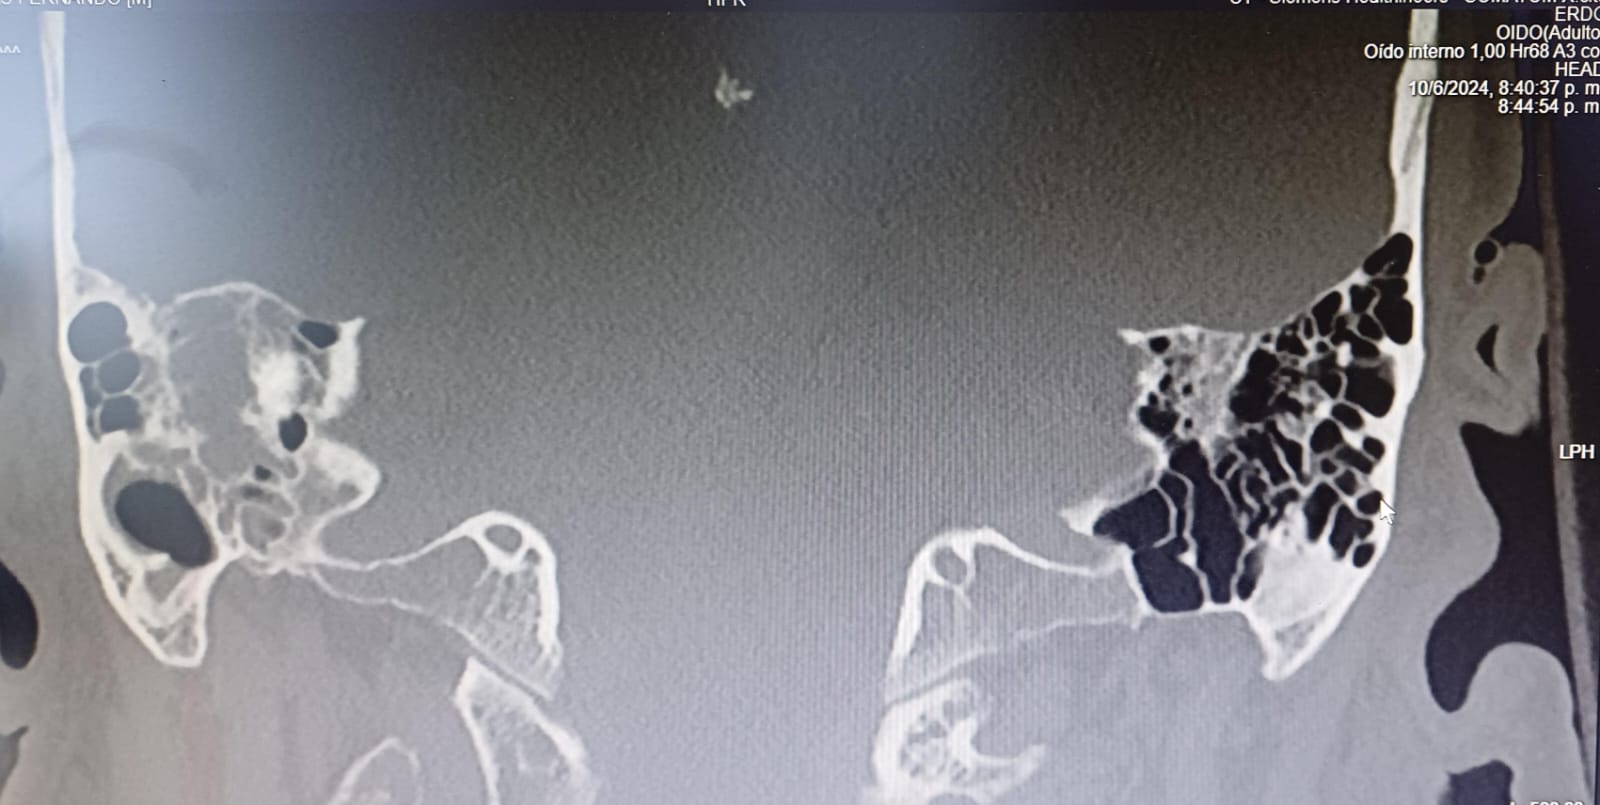

Meningoencefalitis otógena secundaria a OMA. Empiema subdural derecho. Tromboflebitis séptica en seno sigmoide y transverso distal derechos. Hemorragia subaracnoidea.

Manejo conservador conjunto Otorrinolaringología (ORL)y Neurología (NRL). Ante situación clínica se traslada a Unidad de Críticos y posteriormente ingreso en UMI para neurovigilancia con buena evolución. Seguimiento con TC y RNM cráneo y oído presentando ocupación de oído medio y celdillas mastoideas derechas, solución de continuidad en techo de mastoides con gas intracraneal. Empiema subdural en convexidad derecha 6 mm (previo 3 mm). Ante febrícula y leucocitosis mantenida se realiza nueva PL, con incremento de glucorraquia y sin gérmenes, se amplía antibioterapia a meropenem con buena evolución clínica posterior. Alta a planta de NRL con seguimiento por Unidad de Enfermedades Infecciosas.